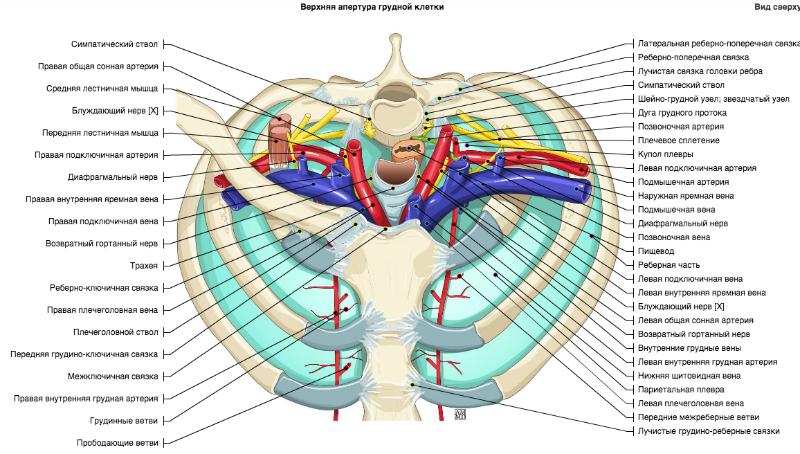

Анатомия Сердца: Расположение и Функции